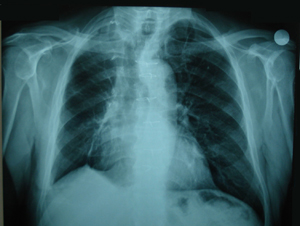

Εικόνα 3α-δ

Αξονική τομογραφία θώρακος σε διαφορετικά επίπεδα. Μάζα μαλακών μορίων που καταλαμβάνει το μεγαλύτερο μέρος του άνω λοβού. Η μάζα πιέζει την πνευμονική αρτηρία, τον κύριο βρόγχο και την άνω κοίλη φλέβα και πρόκειται για μάζα εκ μαλακών μορίων με νεκρώσεις κατά περιοχές.

Α-Β

Γ-Δ